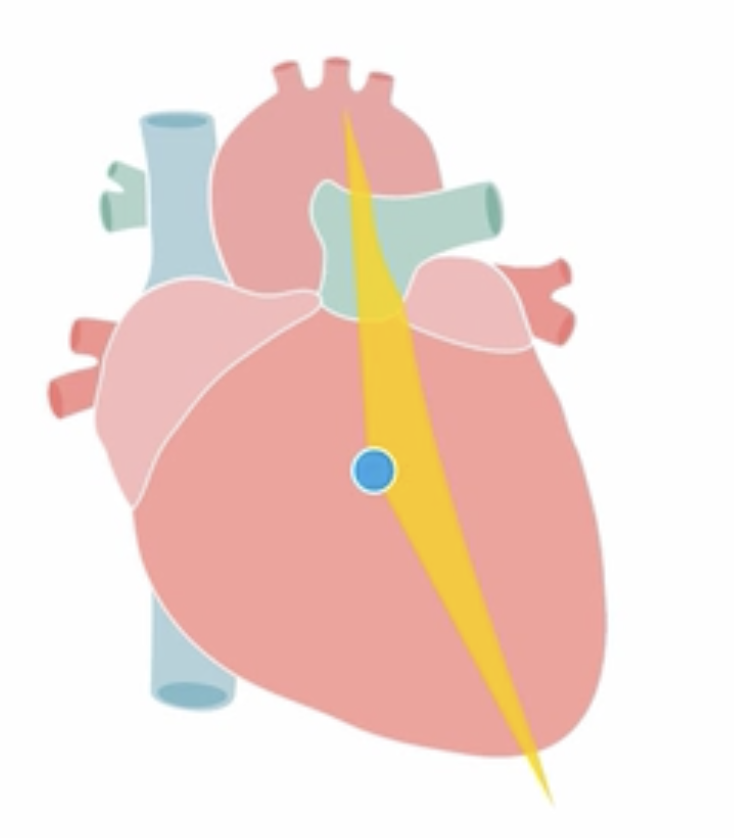

Parasternal Long Axis view

(PLAX)

how to best get the parasternal long axis (PLAX) view?

lie patient on left side, stretch left arm behind head

cardiac probe notch towards right shoulder, at 4th intercostal space

what are you expected to visualise from a parasternal long axis view

A

• RV outflow tract

• Aortic valve -> aorta

• Mitral valve

How well did you know this?

what to assess in the parasternal long axis view?

1. aortic valve:

- use colour doppler to assess for stenosis/ regurgitation

2. mitral valve:

3. LA/LV/Ascending aorta dimensions

4. RV outflow tract

5. Pericardial effusion